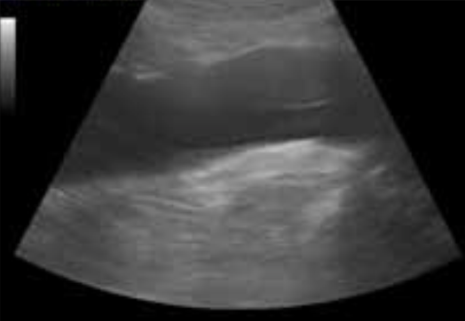

This is a mirror image artifact of what

Hemangioma in the liver